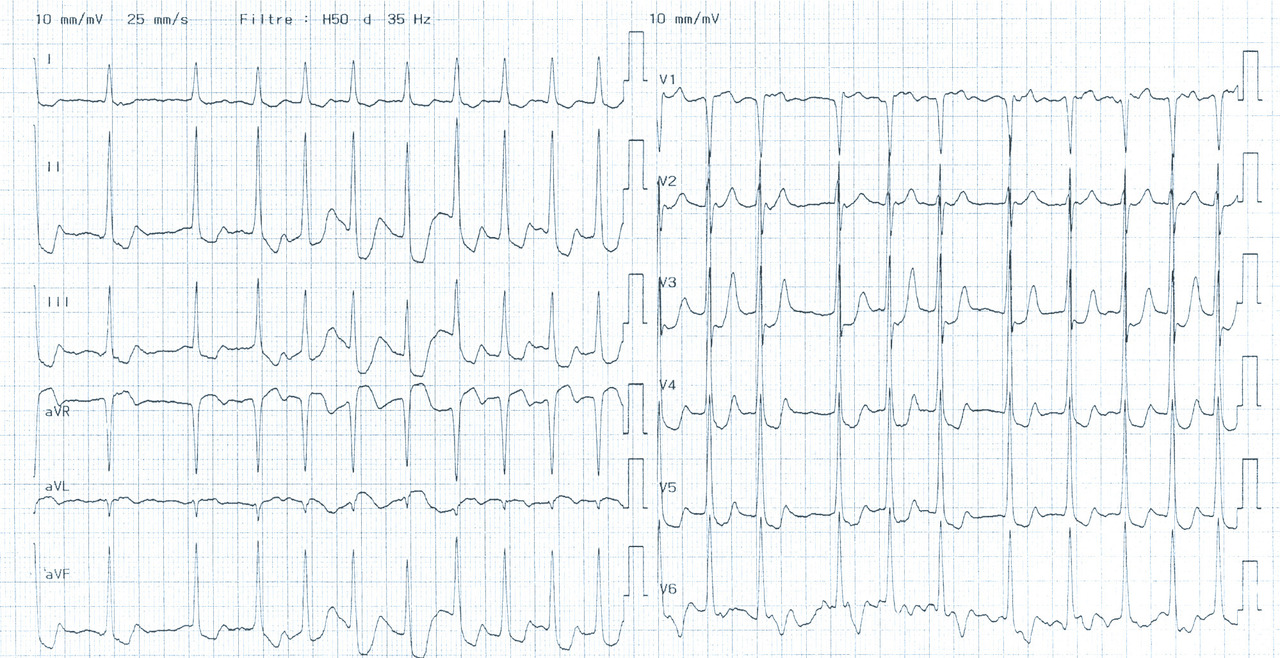

L’ECG 12 dérivations (complété par les postérieures et droites) est réalisé lors du premier contact médical en per- ou post-critique (fig. 11 et 12). Dans plus d’un tiers des cas, il est normal. Le dosage des hs-cTn complète la démarche diagnostique. Le seuil de positivité, défini comme étant le 99e percentile de la valeur limite de référence dans une population de sujets sains, dépend du kit des hs-cTn utilisé et du contexte épidémiologique local. L’algorithme de triage (fig. 13) actuellement recommandé s’appuie sur un dosage des hs-cTn à l’admission (H0) répété 3 h plus tard (H3), sauf si la douleur s’est manifestée ≥ 6 h avant l’admission. La valeur prédictive négative de cet algorithme dans le diagnostic d’IDM est de 99,6 %-100 %.

Patiente de 79 ans avec douleur thoracique et palpitations depuis 2 heures. L’ECG (n° 1) montre une FA avec sous-décalage diffus marqué. Il existe un souffle de rétrécissement aortique. La troponine sera à H+6 à 170 ng/L. Il s’agit d’un NSTEMI mais sur un mécanisme d’IDM de type 2. La réduction de la FA permet une normalisation de la repolarisation (ECG n° 2). La coronarographie ne retrouve pas de sténose > 50 %. Le rétrécissement aortique nécessite un complément de bilan. La prise en charge concerne la FA et le rétrécissement aortique.